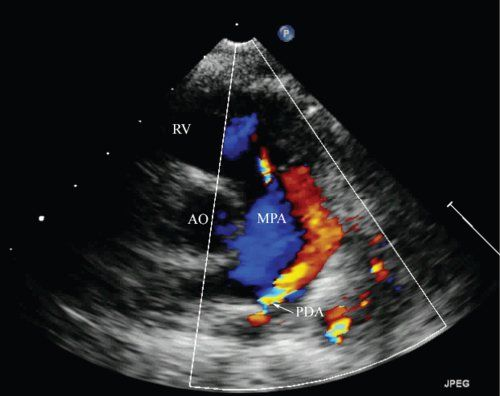

Patent ductus arteriosus

What is seen in this 2D image?

SSN

High basal PSAX

What views can a PDA be seen from (2)?